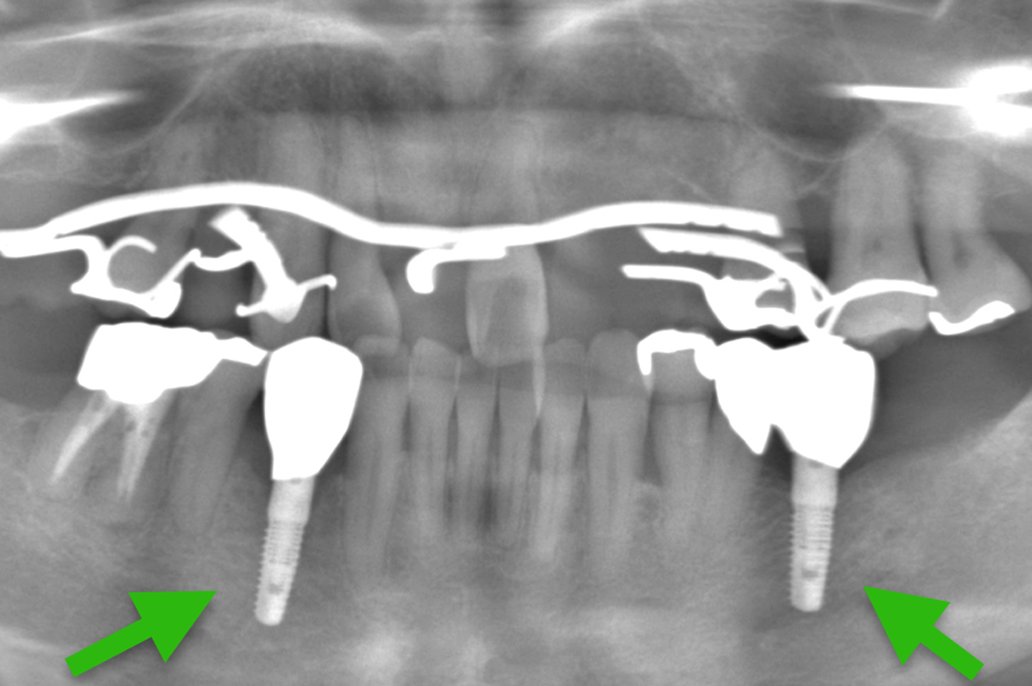

| 主 訴 | 歯がない部分を治療したい |

|---|---|

| 治療期間 | 約6ヶ月 |

| 治療費 | 合計3,278,000円(税込) |

| 治療内容 | 治療1回目 保存不可能な歯の抜歯 治療2回目 CT撮影にて顎の骨にインプラントが入ることを確認し、サージカルガイドの型取り 治療3回目 インプラントを入れる治療 治療4回目 縫合してある糸をとり、周りをクリーニング 治療5回目 インプラントに土台を立てる治療 治療6回目 上部構造(被せ物)の型取り 治療7回目 上部構造(被せ物)をセット |

| 治療のリスク | インプラントの手術の後は腫れ、 痛みが出ることがあり ます。 |